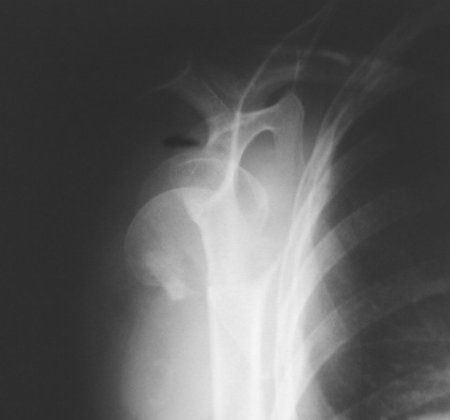

Shoulder X-ray